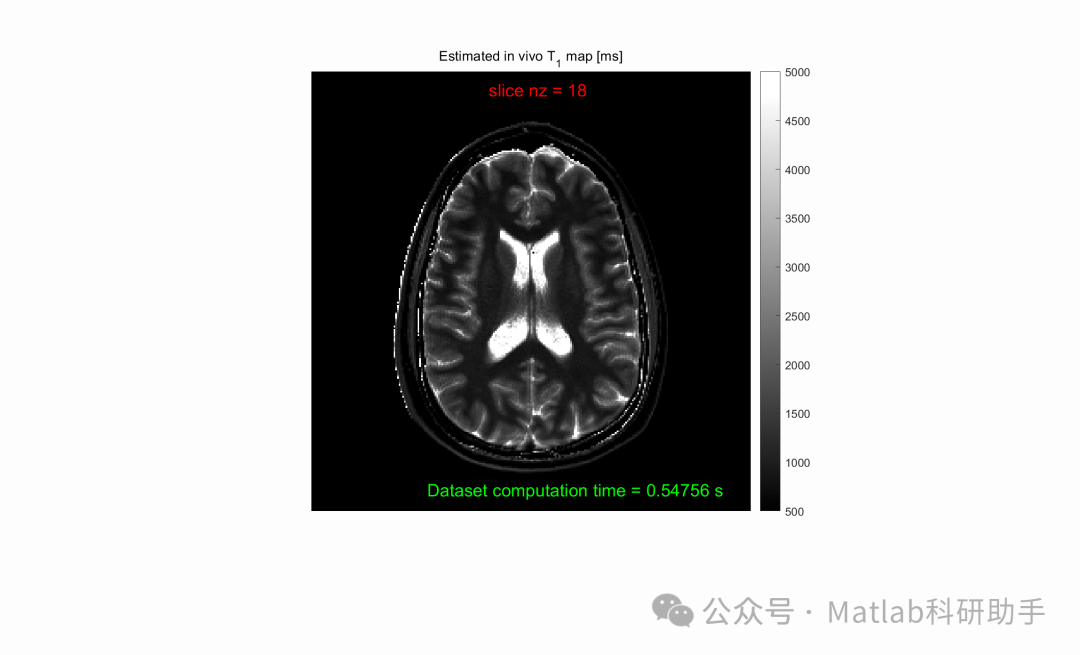

⛳️ 运行结果